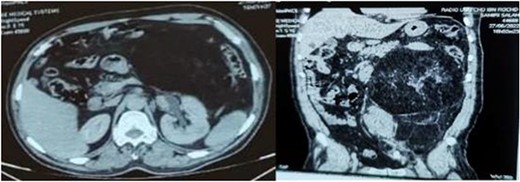

A 58-year-old man presented with an abdominal mass and swelling of the left scrotum that had been evolving for approximately three months. The patient had a good clinical appearance at the time of consultation, with no urinary or digestive complaints reported. Physical examination revealed a large, firm and painless mass occupying the entire left flank. A thoraco-abdomino-pelvic CT scan showed a voluminous retroperitoneal mass of fatty density measuring 20 × 18 × 21 cm simulating a liposarcoma, which communicates with the left inguinal canal and responsible for a left pyelocaliceal dilation (Fig. 1). Complementary inguino-scrotal MRI showed thickening of the scrotal envelopes. Resection of the retroperitoneal tumor via the intercostal approach was difficult, because it was bulky and pushed back the adjacent structures (peritoneum, spleen and left kidney). Its extraction required the opening of the peritoneum and the realization of an extended detachment up to the left colic angle and the release of the left ureter up to its crossing with the iliac vessels. Release of the lower pole of the mass revealed its extension through the left inguinal orifice, and the spermatic cord was hard on palpation. A left inguinal incision was made secondarily to extract the retroperitoneal mass en bloc with the suspect testicle and its cord (Fig. 2). Macroscopically, the mass was encapsulated weighing 4440 g, measuring 30 × 25 × 8 cm, firm, yellow-white with necrotic-hemorrhagic areas. Histology concluded to a dedifferentiated retroperitoneal liposarcoma involving the testis and its spermatic cord; the surgical histological margins were negative. The immediate postoperative evolution was normal (Fig. 3), and up to six months of follow-up.

Axial and sagittal sections of an abdominal-pelvic CT scan showing a retroperitoneal liposarcoma compressing the surrounding structures and responsible for left pyelocaliceal dilation.